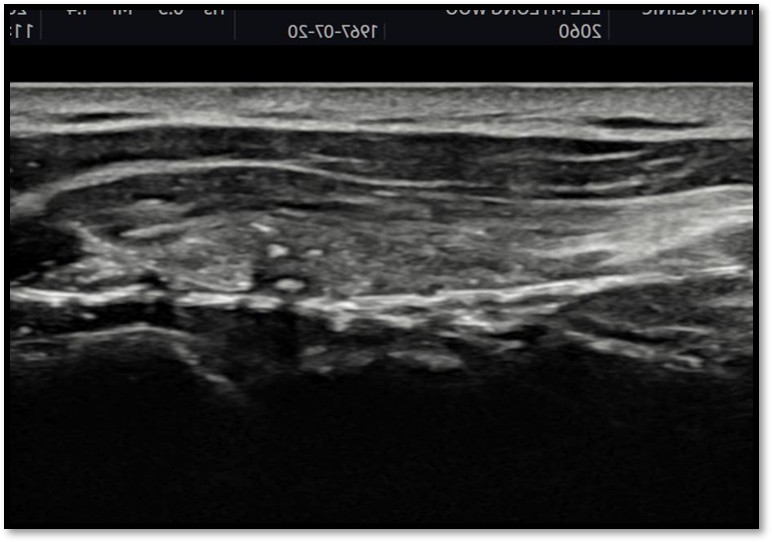

MRI와 초음파를 다시 검토했습니다.

회전근개 극상건의 관절면측(articular-side) 부분파열.

Step 2: 초음파 유도 하 가이드 삽입

초음파로 파열 부위를 실시간 확인하면서 특수 가이드를 삽입합니다.

파열 위치에 정확히 접근